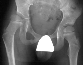

examination he has markedly asymmetrical hip abduction and internal rotation,

a large amount of spasticity in the rectus femoris muscle, and severe planovalgus

feet.

hip subluxation with the windblown deformity is a significant problem with

his current ambulatory difficulty.

option for treatment of this boy is to recommend a femoral varus osteotomy

for the right subluxated hip and subtalar fusions of both feet.